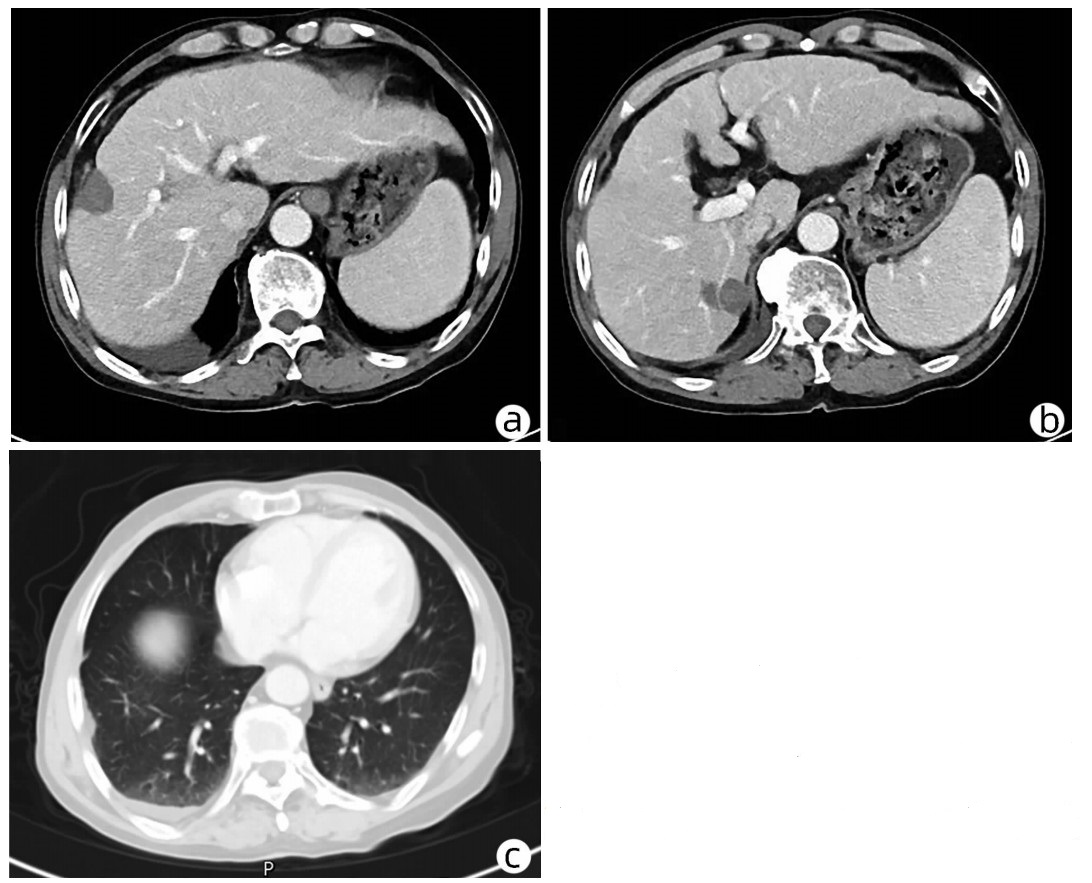

肝细胞癌合并胆管癌栓1例报告

2022, 38(8): 1872-1874. DOI: 10.3969/j.issn.1001-5256.2022.08.028

摘要(803) HTML (455) PDF (3665KB)(82)